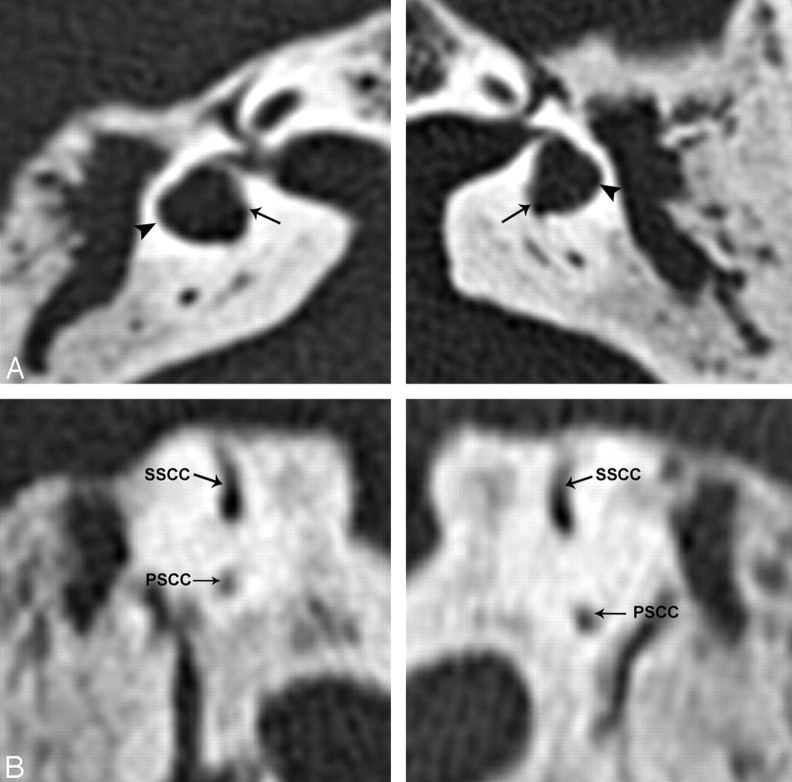

Fig 1.

Axial (A) and coronal (B) 2D CT scans demonstrate dilated dysplastic lateral semicircular canals (arrowheads) with possible dysplastic vestibules (arrows) bilaterally. 2D coronal CT images demonstrate segments of the posterior and superior semicircular canals.